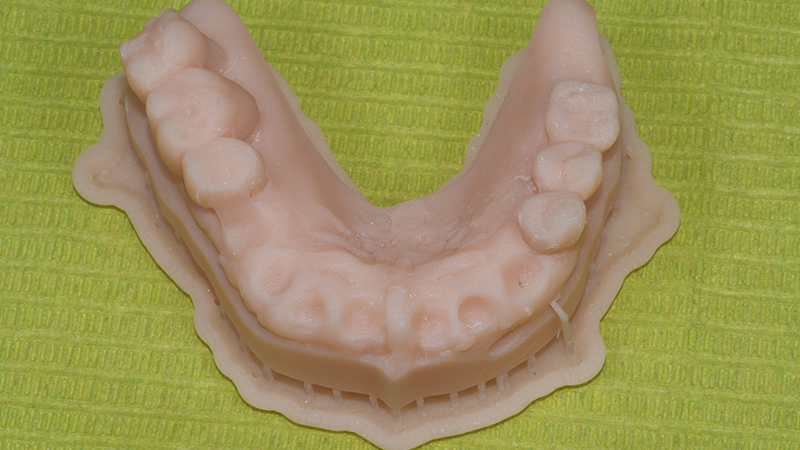

Dopo aver verificato la posizione della dima chirurgica sul modello digitale stampato, quest’ultima è stata posizionata in bocca tramite il supporto dentale dei settori latero-posteriori ed un pin di fissaggio è stato applicato (Anchor Pin Kit, Megagen, Daegu, Corea del Sud) (Figs. 7, 8, 9)

Modello digitale stampato

Fig. 7 - Modello digitale stampato